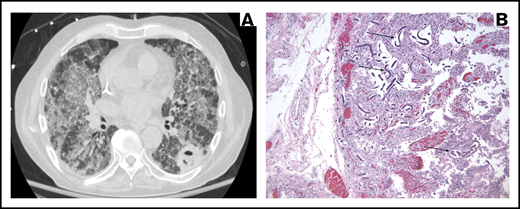

A 71-year-old man with high-grade myelodysplastic syndrome underwent nonmyeloablative allogeneic HCT with a peripheral blood allograft from an HLA-matched unrelated donor in 2016. Two months pre-HCT, a chest CT scan demonstrated multiple bilateral pulmonary nodules. The largest nodule (2.3 × 1.7 × 2 cm) in the right upper lobe was biopsied. Pathology demonstrated diffuse alveolar damage; all infectious workup including cultures and fungal serologies and antigens were negative. He was treated empirically with voriconazole and a repeat chest CT scan 1 month pre-HCT showed near complete resolution of the nodules. Voriconazole was continued post-HCT as secondary prophylaxis. Two months post-HCT, he was diagnosed with acute gut GVHD for which he was started on prednisone 2 mg/kg daily with subsequent taper. Three months post-HCT, while on prednisone 20 mg daily, he developed progressive dyspnea on exertion and a petechial rash on his abdomen and back. He was admitted (HD0) and found to be tachycardic, hypotensive, and hypoxic, but afebrile. Laboratory results were pertinent for worsening anemia. He rapidly decompensated from hypoxic respiratory failure. Chest CT scan demonstrated new, bilateral diffuse ground-glass opacities and a superimposed cavitary lesion/abscess in the left lower lobe (Figure 4A). Voriconazole was changed to liposomal amphotericin B, and he was started on TMP-SMX in conjunction with high-dose steroids. On HD1, he was intubated electively for bronchoscopy, which revealed evidence of diffuse alveolar hemorrhage (DAH). His clinical status continued to decline despite maximal supportive measures. He was transitioned to comfort care and died on HD12.

Images corresponding to illustrative case 3 (missed parasitic disease). (A) Chest CT scan demonstrating bilateral diffuse ground-glass opacities and a superimposed cavitary lesion/abscess in the left lower lobe. (B) Sections of the duodenum (original magnification ×10) with hematoxylin and eosin stain showing obliteration of the inner mucosa by S stercoralis larvae (arrows).

Autopsy revealed diffuse bilateral acute pulmonary S stercoralis disease, invasive S stercoralis duodenitis (Figure 4B), and an isolated left lower lobe 3.5 cm cavity with fungal elements due to Mucorales. Postmortem review of his chart for Strongyloides risk factors revealed that he was an Army veteran who had served in the Vietnam War for 11 months at least 40 years prior to his death.

Careful attention should be paid to radiographic patterns when generating a differential diagnosis. This patient had 2 distinct radiographic patterns on chest CT scan, with the bilateral ground-glass opacities corresponding to DAH due to S stercoralis and the left lower lobe cavitary lesion/abscess corresponding to mucormycosis. This case again illustrates that HCT patients can have multiple concomitant infections with major clinical significance.